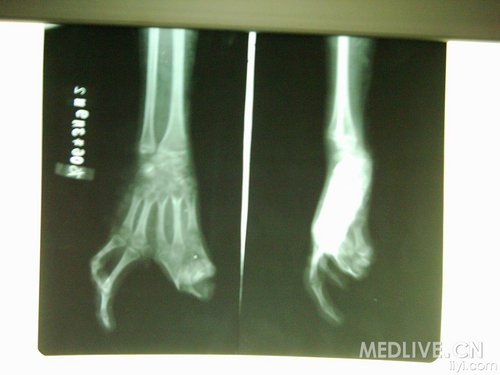

这是什么病,有图大家一起讨论

这是什么病

看起来应该是树人症